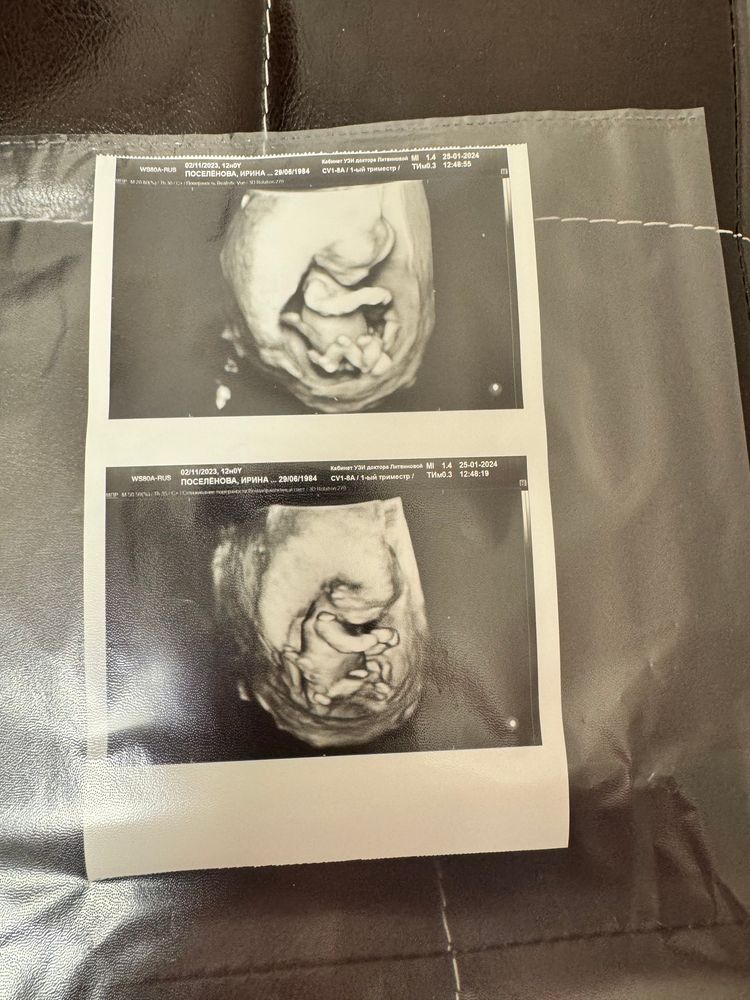

Виктория, всё хорошо) снимок сделали в Изображение 5 д)

Ирина, огоо 🥰😍 у меня 2д только 😄 классический . какой крошка 🫶👼